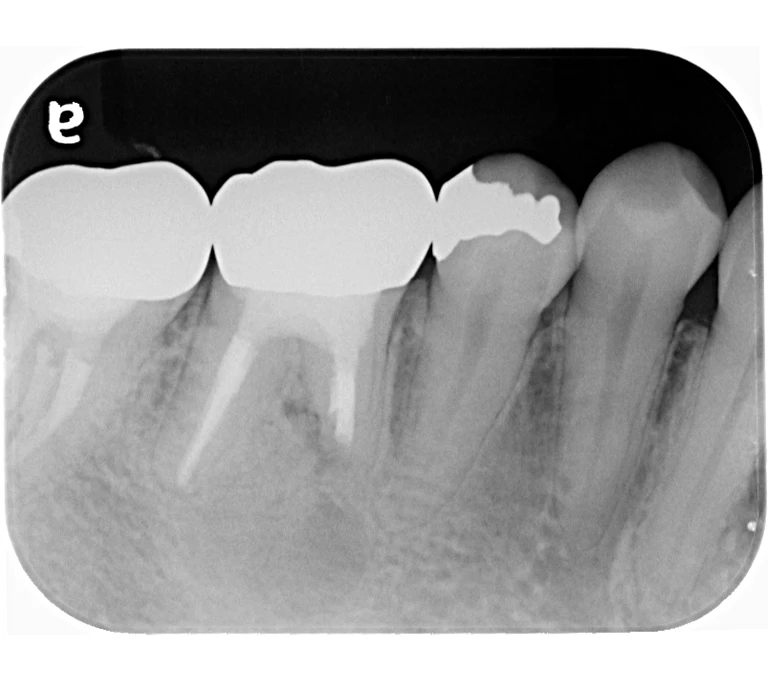

治療前

治療後

| 主訴 | 右下奥歯が痛い。 他院で『膿の袋が大きいため抜歯』と言われセカンドオピニオン希望でご来院。 |

|---|---|

| 治療期間 | 約半年(6か月) |

| 治療費 | 約5万円 |

| 治療内容 | ラバーダム、マイクロスコープ下にて根管治療を実施し、歯根端切除を行う。歯茎の腫れは消失し違和感や痛みも消失した。 |

| 治療のリスク | マイクロスコープやCTを使用し、可能な限り精密な根管治療を行っていますが、歯根の形態や病変の大きさ、過去の治療履歴などにより、治癒が得られない場合があります。 また、治療後に再感染や歯根破折が生じることもあり、その場合は再治療や抜歯が必要となることがあります。 治療結果には個人差があり、すべての症例で同様の経過を保証するものではありません。 |